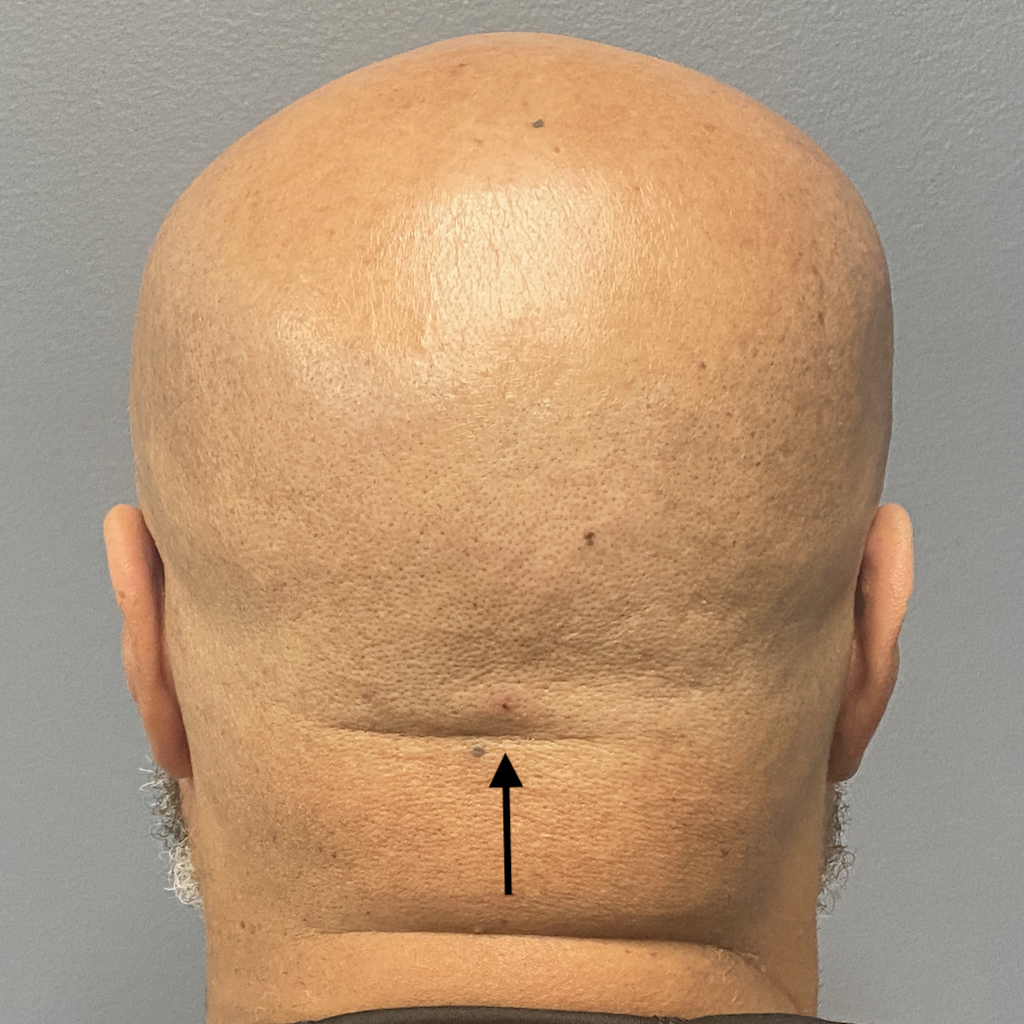

Patient 61

Desire for less wide sides of the head.

Head narrowing surgery performed by removal of posterior temporal muscle through postauricular incisions.

Desire for less wide sides of the head.

Head narrowing surgery performed by removal of posterior temporal muscle through postauricular incisions.